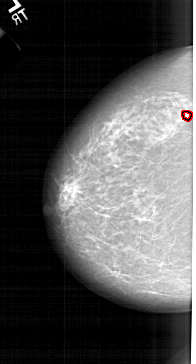

A_1214_1.LEFT_MLO

FILE: A_1214_1.LEFT_MLO.OVERLAY

TOTAL_ABNORMALITIES 1

ABNORMALITY 1

LESION_TYPE CALCIFICATION TYPE PLEOMORPHIC DISTRIBUTION CLUSTERED

ASSESSMENT 4

SUBTLETY 4

PATHOLOGY MALIGNANT

TOTAL_OUTLINES 1

BOUNDARY